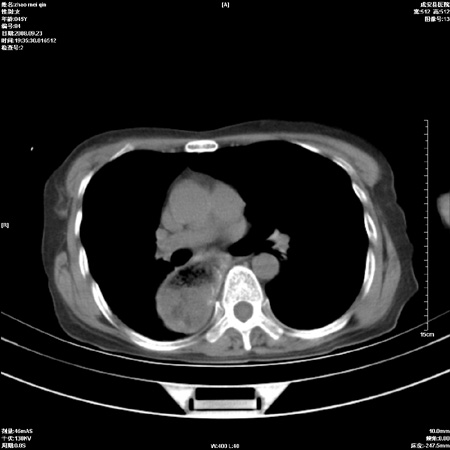

标题: CT15861:女 60 外伤后1小时 胸疼 [打印本页]

标题: CT15861:女 60 外伤后1小时 胸疼

外伤后1小时 胸疼 是外伤后引起的吗?

食道扩张明显下端逐渐变窄,倒像贲门失迟缓

食道ca术后胸腔胃,右肺挫伤?

非外伤性改变,典型的贲门失迟缓症

食道扩张明显下端逐渐变窄,大量食物存留,象贲门失迟缓症。